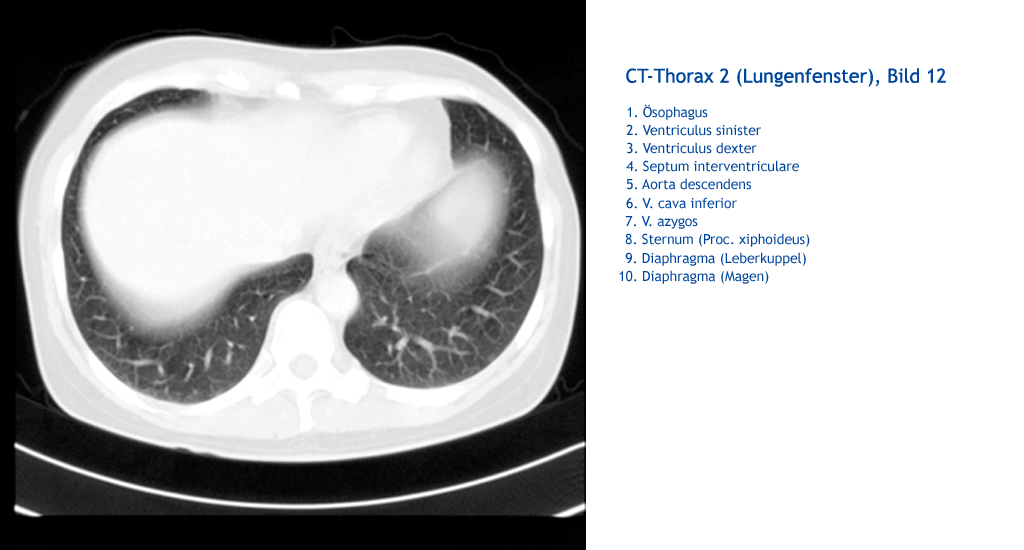

Diaphragma (Magen) Diaphragma (Leberkuppel) Sternum (Proc. xiphoideus) V. azygos V. cava inferior Aorta descendens Septum interventriculare Ventriculus dexter Ventriculus sinister Ösophagus